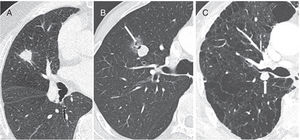

Nodules with a high risk for malignancy. (A) A 70-year-old man with a solid nodule with spiculated margins in the right upper lobe. (B) Part-solid nodule with signs of pseudocavitation (arrow). (C) An 85-year-old man with extensive emphysema and solid nodule with lobulated margins in the left upper lobe (arrow). In all three cases, biopsy was indicated. In (A) and (C), the diagnosis was squamous cell carcinoma, and in (B) invasive adenocarcinoma was diagnosed.